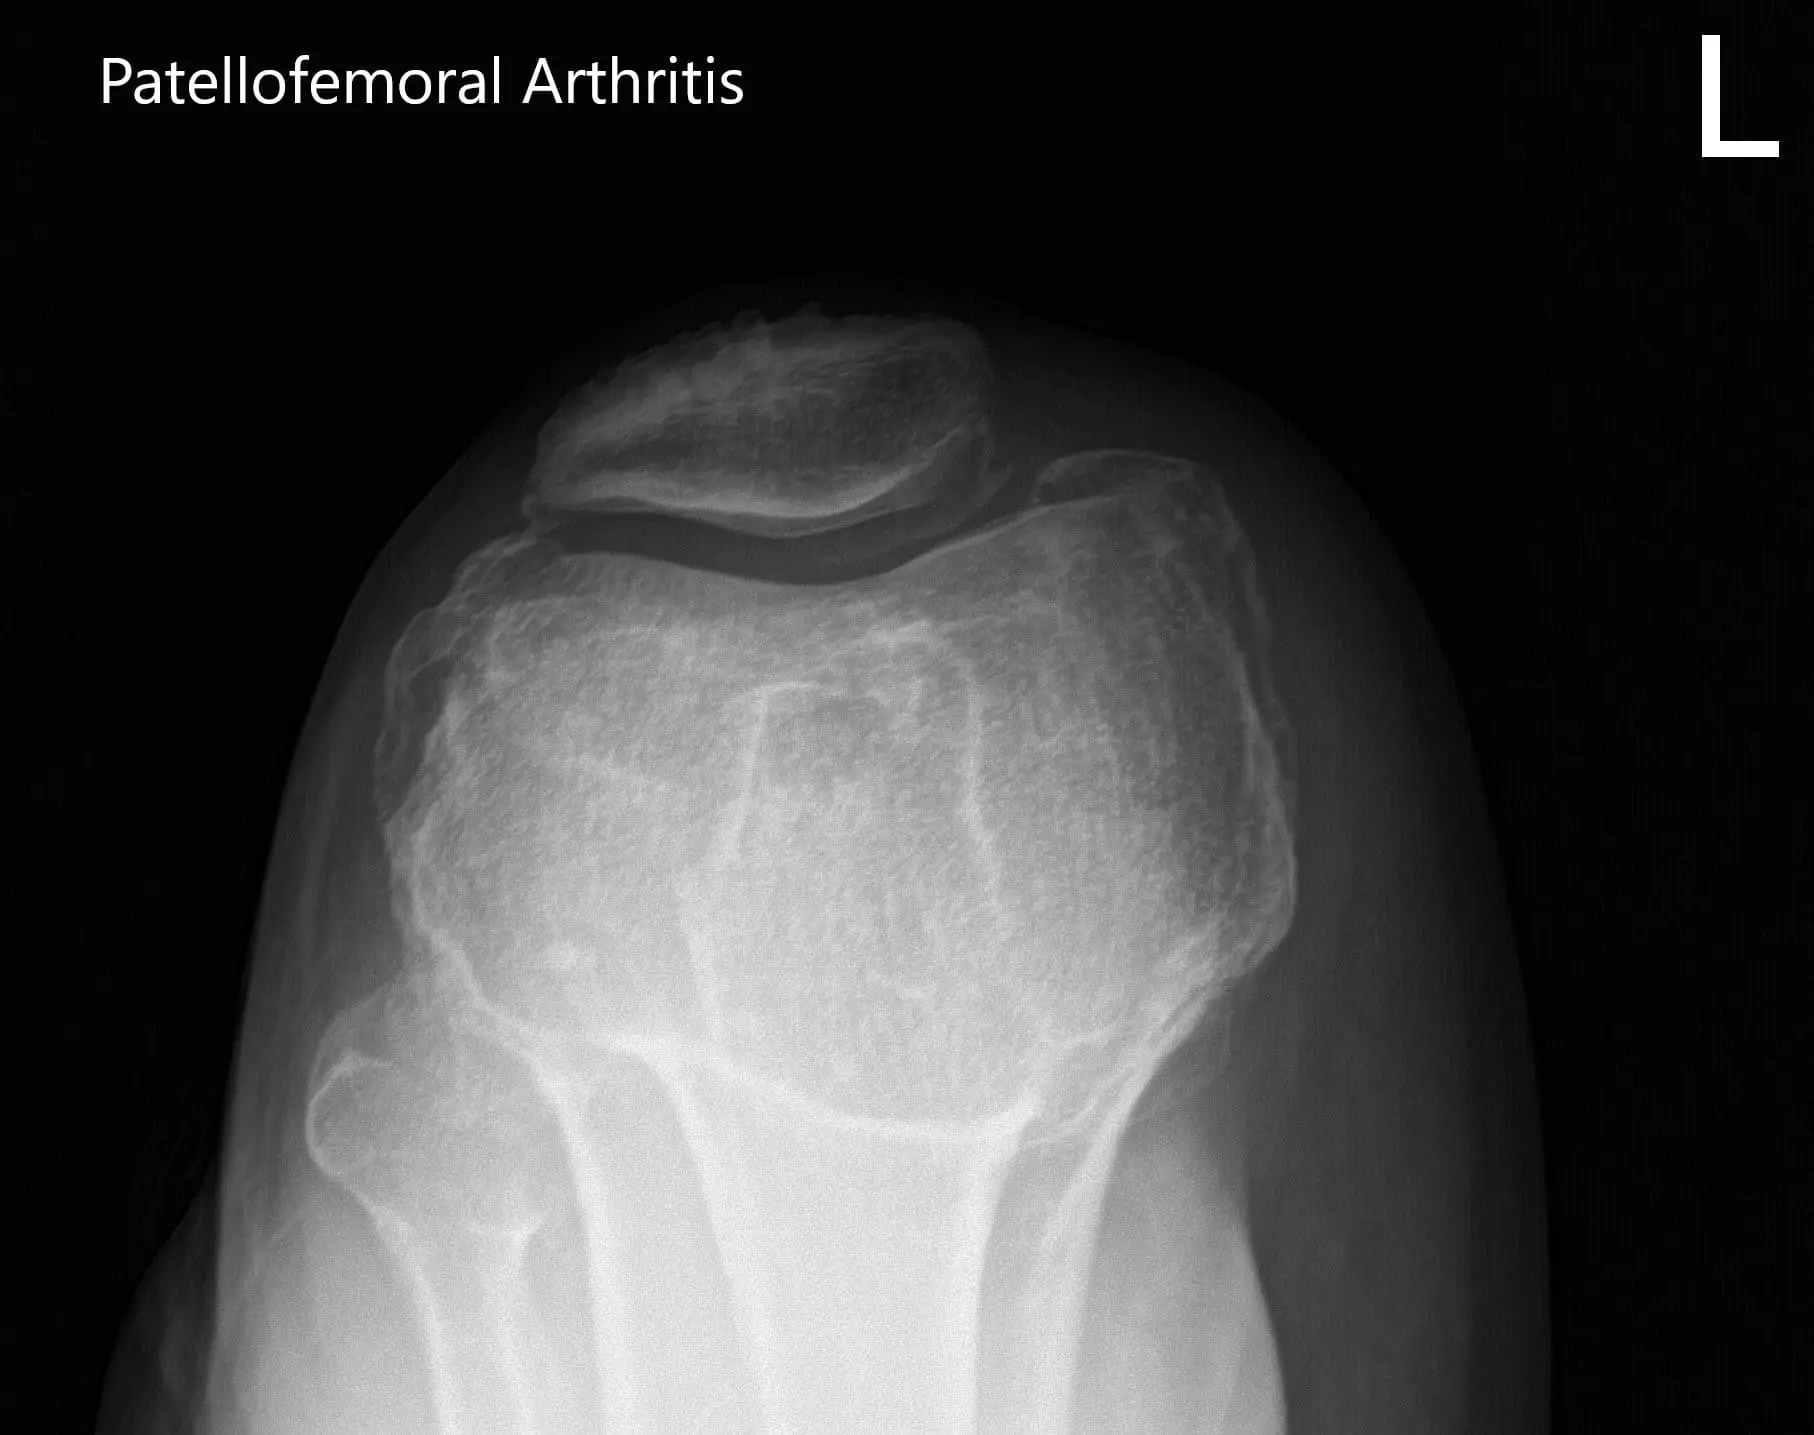

Preoperative X-ray of the left knee showing AP, lateral and merchant views

Preoperative X-ray of the left knee showing AP, lateral and merchant views - img 2

Preoperative X-ray of the left knee showing AP, lateral and merchant views - img 3

There was no distal neurological deficit and the bilateral pulses were good volume and comparable. Imaging studies revealed severe tricompartmental osteoarthritis of the left knee. Considering the patient’s lifestyle limiting knee pain, she was advised customized left knee total replacement. Risks, benefits, and alternatives were discussed with her at length. She agreed with the plan.